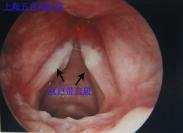

鼻息肉是鼻部常見疾病,也與某些全身疾病有關。它是由于鼻粘膜長期炎性反應引起組織水腫的結果。鼻息肉多來源于中鼻道竇口、鼻道復合體和篩竇,高度水腫的鼻粘膜由中鼻道、...